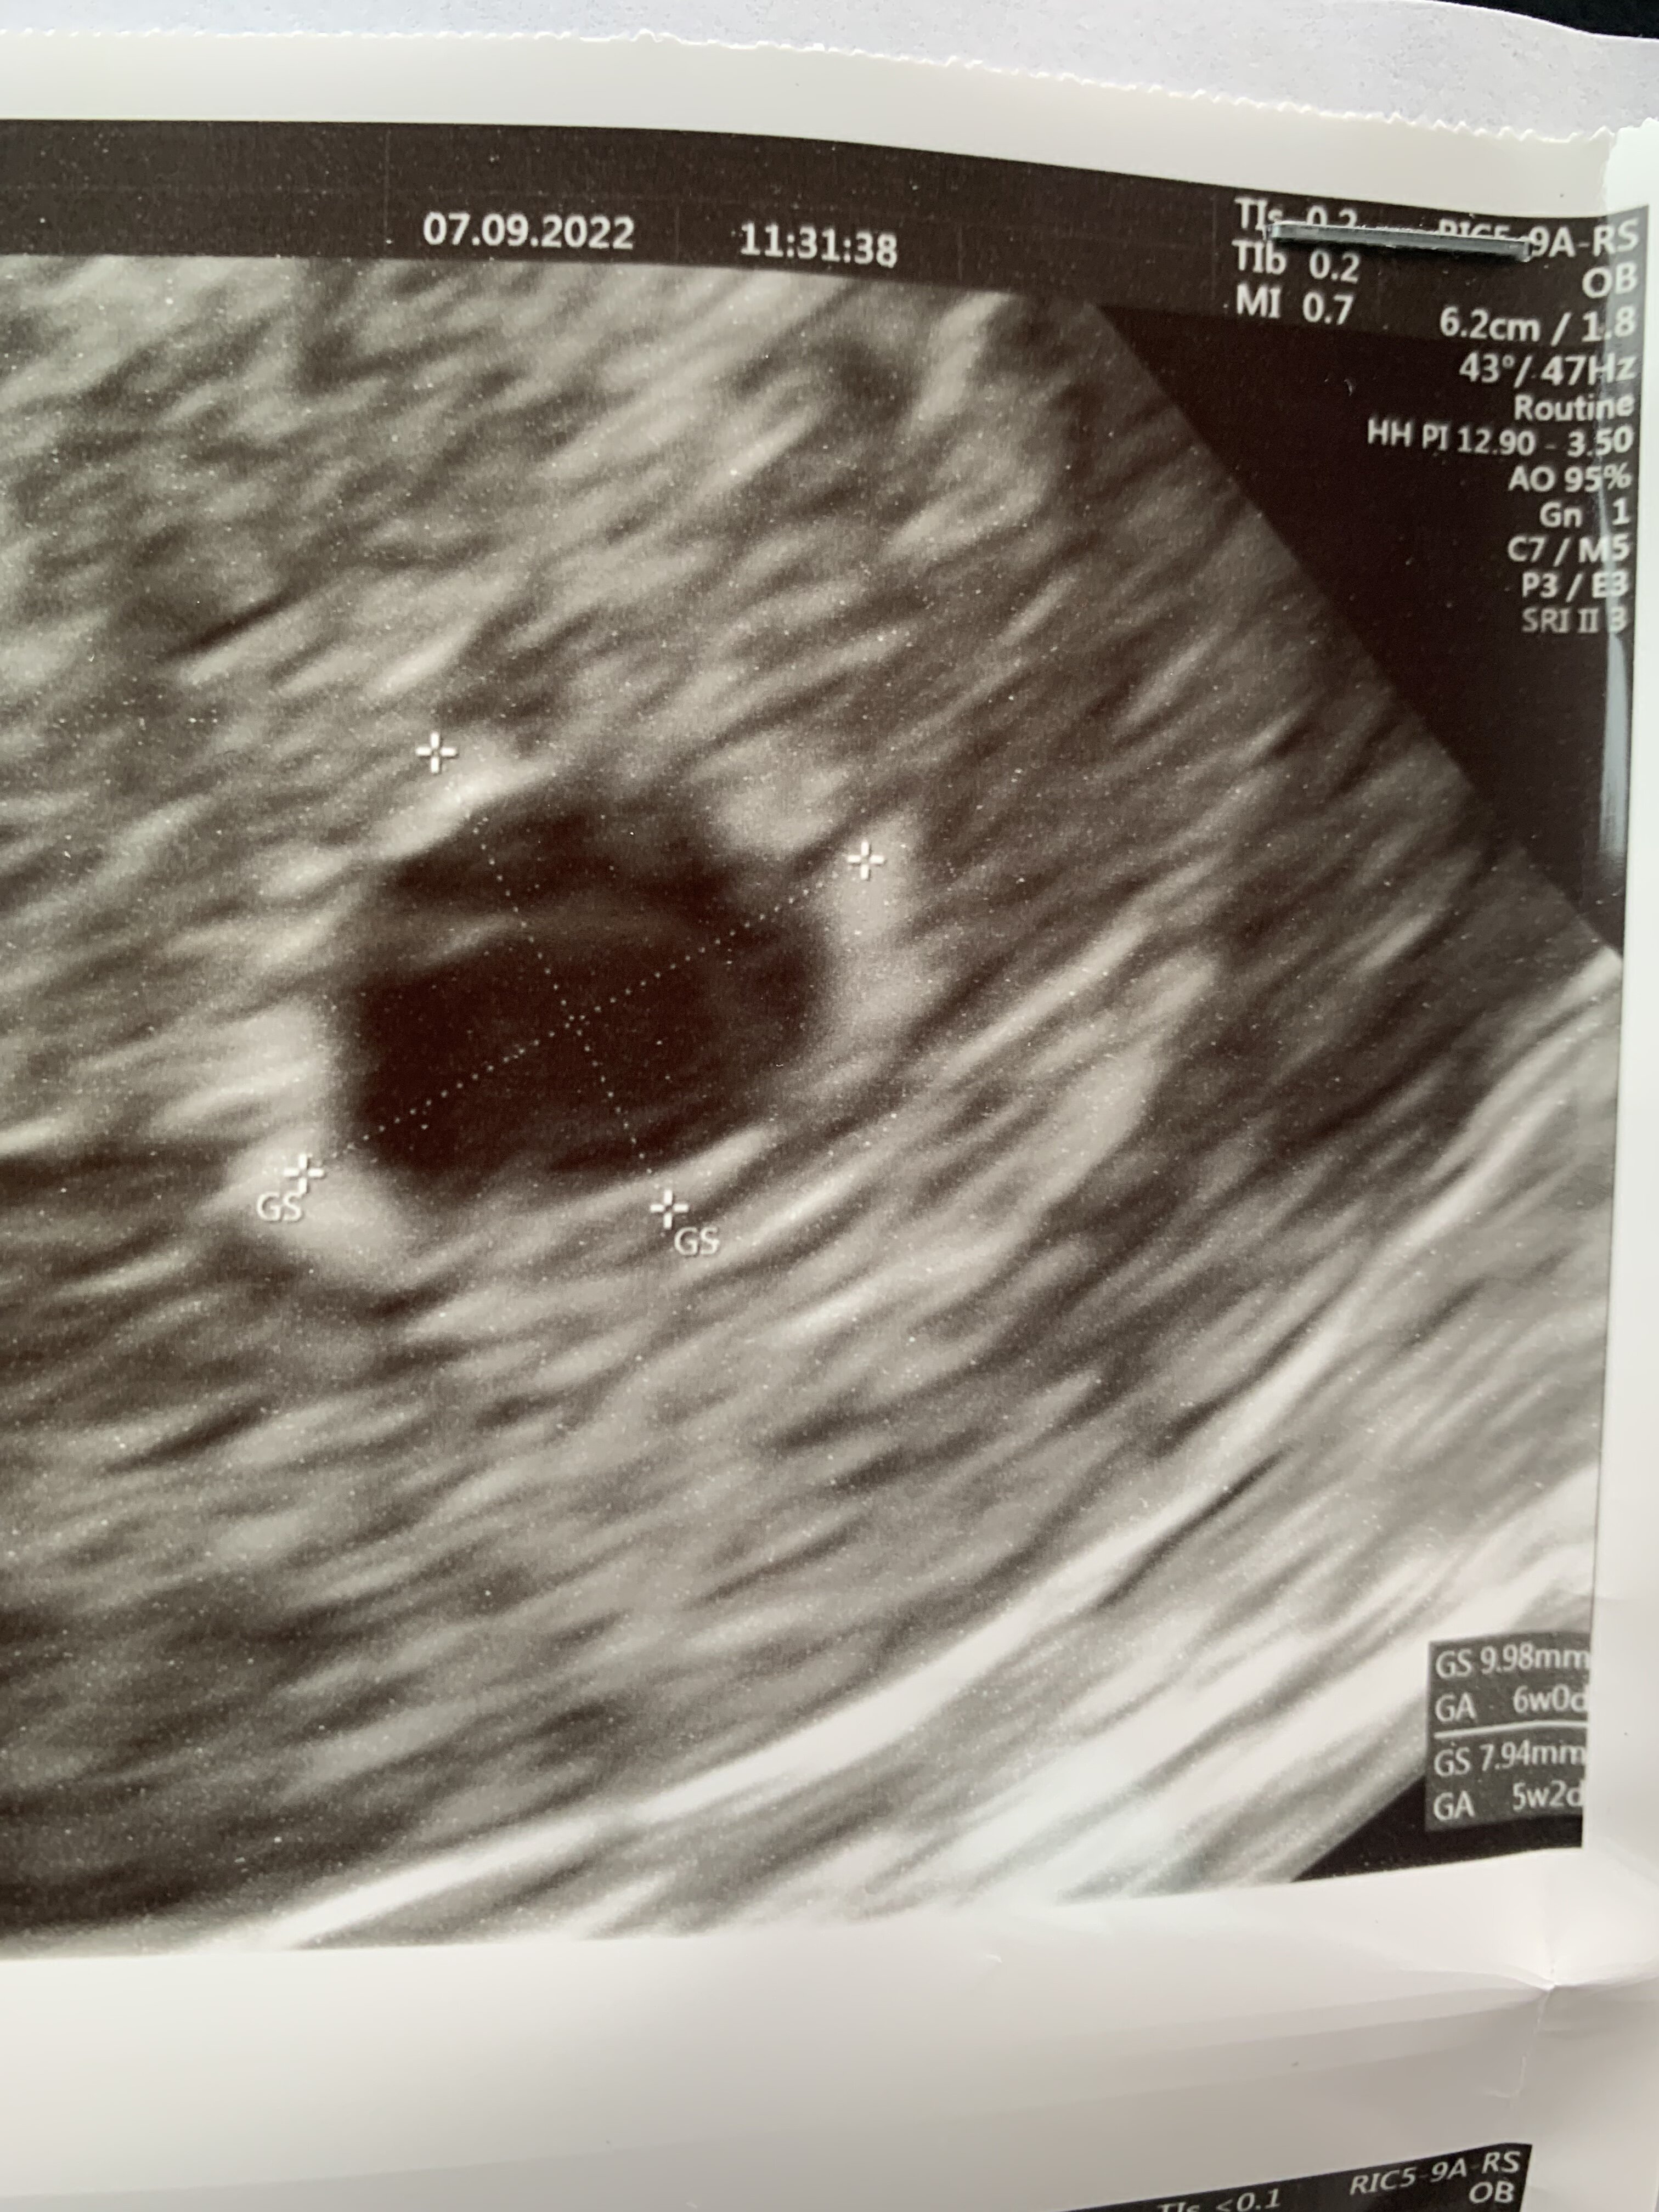

Dziewczyny 7 wrześni byłam na pierwszym usg. W macicy widoczny pęcherzyk ciążowy o wym 9,98 x 7.94. Brak pęcherzyka żółtkowego. Następne usg 19 września. Ostatnia miesiączka 25 lipca. Przeważnie cykle 31-33 dni. Myślicie, że jest szansa że pijawi się jeszcze pęcgerzyk żółtkowy i zarodek. Na usg widać w pęcherzyku jakąś dziwna smuge. Beta w dniu usg ponad 4600

• F0E24354-6E07-40A2-BF5B-344EBDBEE6B4.jpeg

F0E24354-6E07-40A2-BF5B-344EBDBEE6B4.jpeg

1,3 MB · Wyświetleń: 88